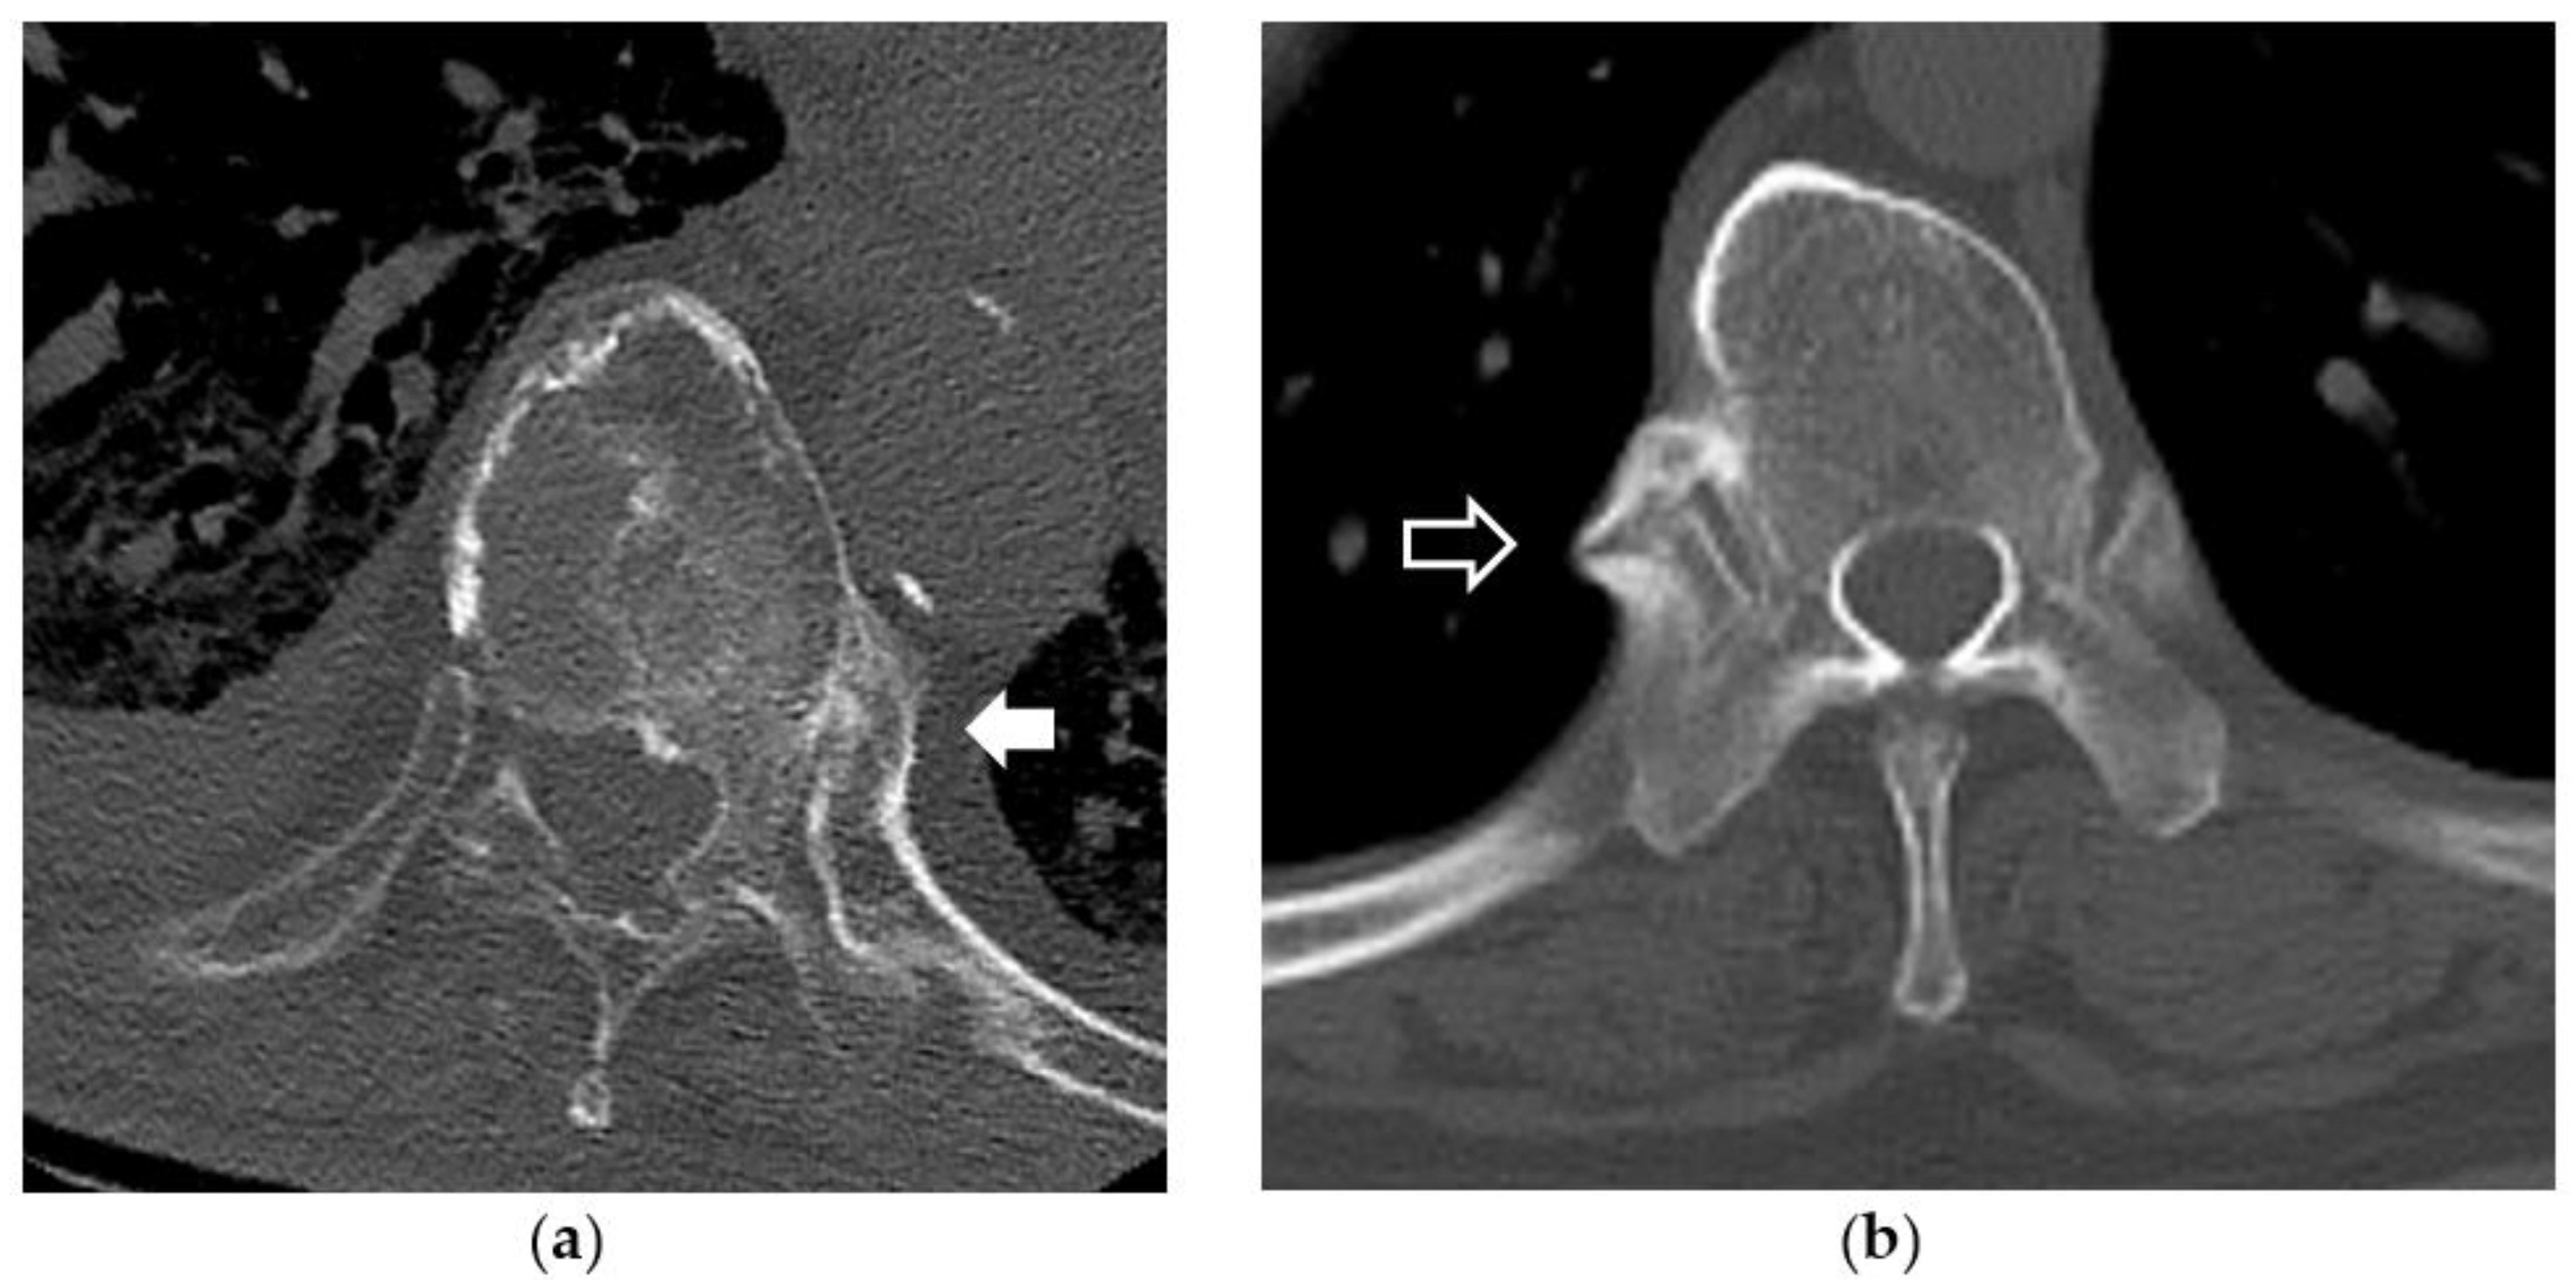

2.2. Imaging Evaluation of DISH

2.5. Evaluation of Hyperostosis around the Costovertebral Joint